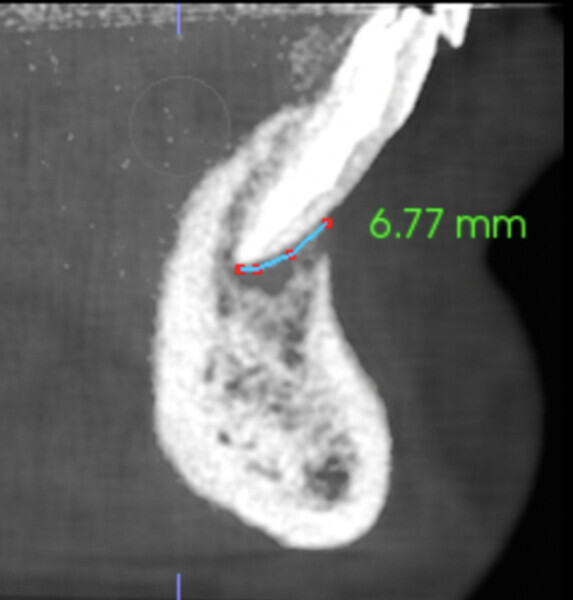

A comparison of the i-CAT scans taken preoperatively and at the nine-month and 18 month follow-ups showed complete regeneration of the cortical and trabecular bone in great biological detail, showing even the groove of the frenum (Figs. 7 & 8). The bone view clearly showed the preoperative major horizontal and vertical bone defect and open periodontal defect, the beautifully regenerated, natural looking bone and the emergence of the mandibular nerve. Happily, the bone continued growing vertically (Fig. 9).

Figs. 9a–f: Comparison of the vertical views of the i-CAT scans taken pre-op (a & b) and at the nine-month follow-up (c & d) and 18-month follow-up (e & f), showing continued growth of the bone vertically.